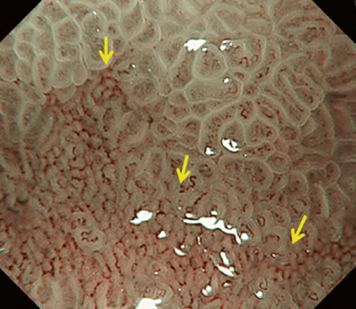

The VS classification system developed by the author (Kenshi Yao) [1] is the most widely accepted diagnostic system for magnifying narrowband imaging (M-NBI) of the stomach [2]. The VS classification system employs anatomical terms as endoscopic markers for analysis. Anatomical components visualized using M-NBI were divided into microvascular (MV) and microsurface (MS) patterns. As shown in . Fig. 1a–c, the subepithelial capillary and collecting venule were visualized for MV pattern, while the marginal crypt epithelium (MCE), crypt opening (CO), and intervening part (IP) between the crypts were identified for the MS pattern. In addition, in terms of the pathological status, the light blue crest [3] and white opaque substance [4] can be markers for microsurface patterns.

According to the morphology of the anatomical components, the MV and MS patterns were classified as regular, irregular, or absent (. Fig. 2). In principle, the MV and MS patterns must be determined separately.